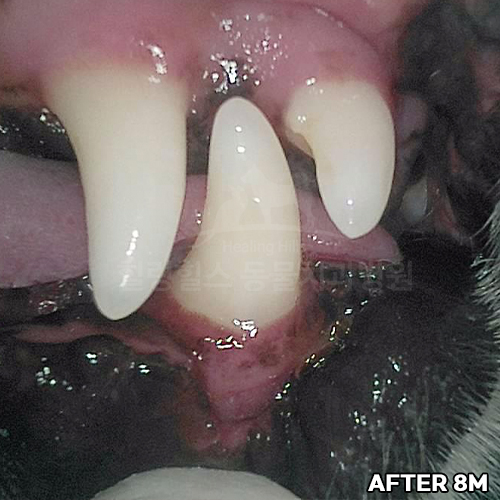

[강아지 치주치료 후 8개월 경과]